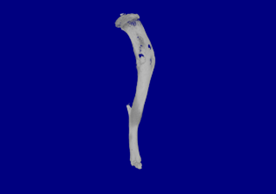

裸鼠胫骨肿瘤浸润模型